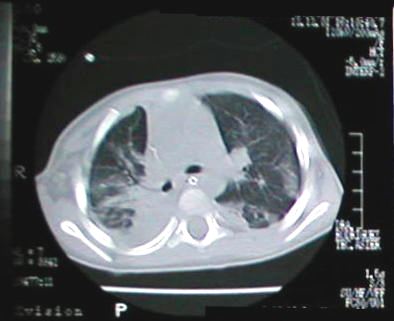

Corte Tomográfico " 2 "

Corte 2 cm por debajo al anterior:

Areas neumonicas bilaterales y el engrosamiento pleural derecho por paqui-pleuritis.